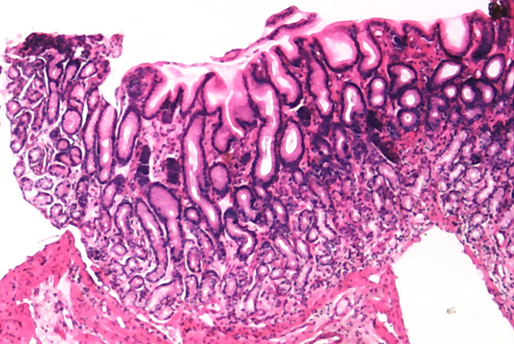

肠化的胃粘膜